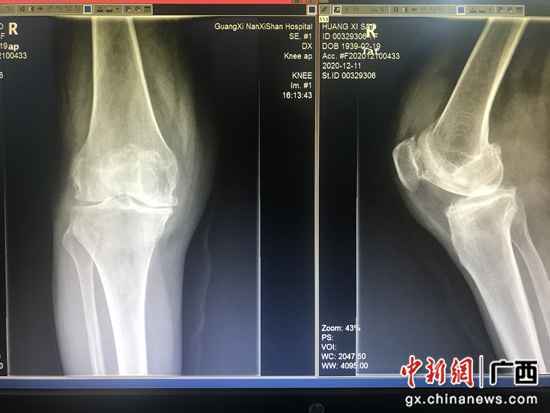

术前X线照片提示枢纽间隙变窄、枢纽软骨受损。南溪山医院供图 黄奶奶入院后,脊柱骨病外科主任医师吴石奇教育的团队为她举办了全面的查抄和评估,认为她年数大,右侧膝枢纽病变严重,颠末多次守旧治疗方案疗效不佳,最终抉择为她实施膝枢纽置换手术。 颠末术前具体筹划,术中密切地团队协作,黄奶奶的手术很乐成,在医护人员悉心照顾下,她术后3天就能下床勾当了,“我能在助行器的帮助下行走自如,腿脚也变得机动了,办理了困扰本身多年的病魔,感受本身变得年青了!”黄奶奶兴奋地竖起大拇指传颂道。